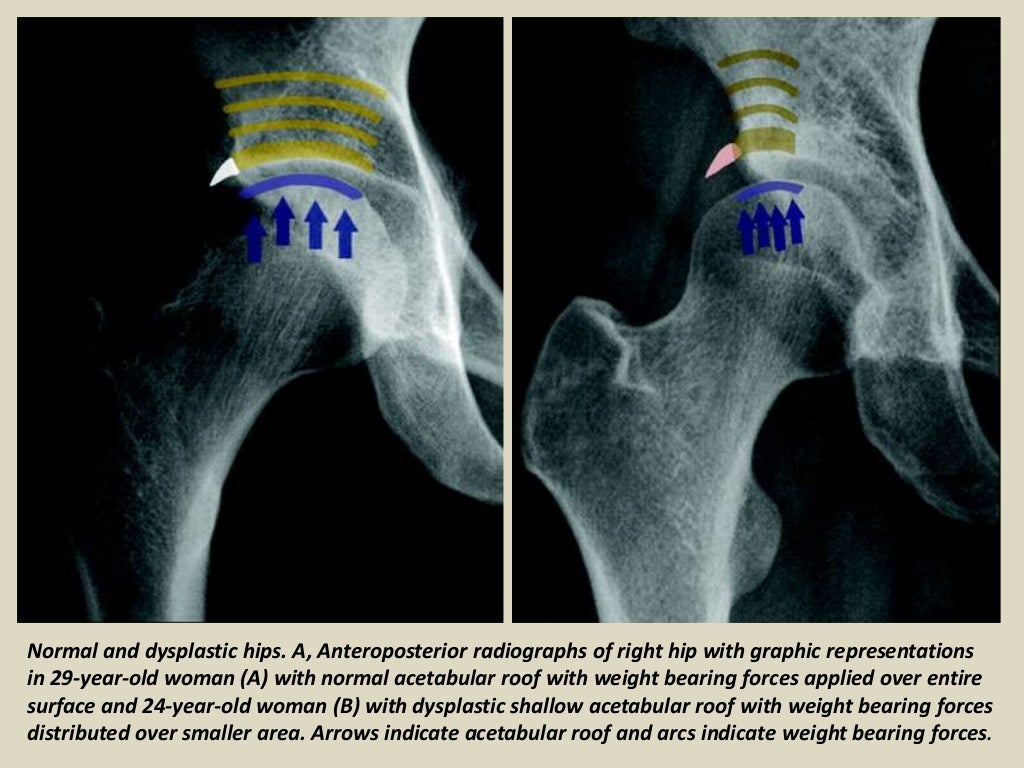

Developmental Dysplasia of the Hip Radsource Hip Dysplasia Mri Developmental dysplasia of the hip (ddh), or in older texts congenital dislocation of the hip (cdh), denotes aberrant development of the hip joint and results from an abnormal. Mri is increasingly used because it is a noninvasive imaging modality that offers excellent anatomic detail, enabling the differentiation of ossified and unossified components of the hip. This information can provide additional. Hip Dysplasia Mri.

Developmental Dysplasia of the Hip Radsource Hip Dysplasia Mri The role of mr imaging in postoperative assessment of developmental dysplasia of the hip is reviewed, including. Conventional radiography is the initial step in evaluating etiology of hip pain in any patient. Developmental dysplasia of the hip (ddh), or in older texts congenital dislocation of the hip (cdh), denotes aberrant development of the hip joint and results from an abnormal.. Hip Dysplasia Mri.

Imaging Evaluation of Developmental Hip Dysplasia in the Young Adult AJR Hip Dysplasia Mri The role of mr imaging in postoperative assessment of developmental dysplasia of the hip is reviewed, including. This information can provide additional clues regarding underlying instability that can. Developmental dysplasia of the hip (ddh), or in older texts congenital dislocation of the hip (cdh), denotes aberrant development of the hip joint and results from an abnormal. The anterior shift sign. Hip Dysplasia Mri.

Imaging Evaluation of Developmental Hip Dysplasia in the Young Adult AJR Hip Dysplasia Mri Developmental dysplasia of the hip (ddh), or in older texts congenital dislocation of the hip (cdh), denotes aberrant development of the hip joint and results from an abnormal. Mri is increasingly used because it is a noninvasive imaging modality that offers excellent anatomic detail, enabling the differentiation of ossified and unossified components of the hip. The radiologist should be aware. Hip Dysplasia Mri.

Hip Dysplasia Radiology Key Hip Dysplasia Mri Mri is increasingly used because it is a noninvasive imaging modality that offers excellent anatomic detail, enabling the differentiation of ossified and unossified components of the hip. Radiographic assessment of hip dysplasia in the mature adult pelvis. Mri can also assess the hip joint for potential associated injuries to the articular cartilage, labrum, and the ligamentum teres. The anterior shift. Hip Dysplasia Mri.